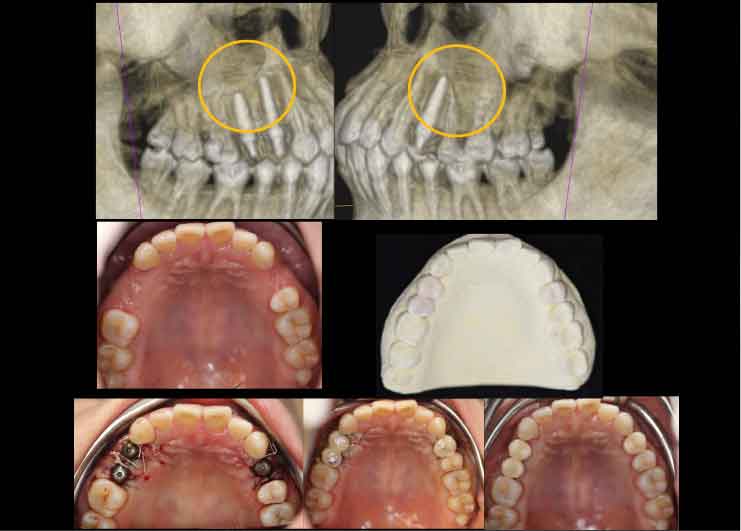

Case1. 21歳女性

生まれつき上あごの3本の歯が欠損しており、骨の幅が少ないケース。

X-ガイド使用により、上あごの上方にある上顎洞を避けた手術を行いました。

CTスキャンを撮影後、DTX Studioによる手術シミュレーションを行い、X-ガイドによるナビゲーション手術を行いました。

CTスキャンを撮影後、DTX Studioによる手術シミュレーションを行い、X-ガイドによるナビゲーション手術を行いました。

Case3. 65歳女性

歯周病でインプラント、歯が脱離。

上あごの骨が非常に薄く、そのままではインプラントを埋め込むことができないため、Xマークを使用したザイゴマ(頬骨)インプラントおよびプテリゴイド(蝶形骨)インプラントを行ったケース。